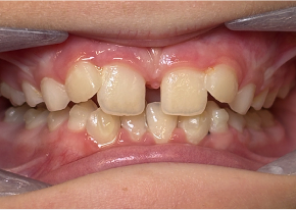

Étude de cas 1

10 ans et 0 mois, 18 étapes d’appareils d’expansion palatine Invisalign

Avec l’aimable autorisation de la Dre Sandra Khong Tai

Avant le traitement d’expansion avec les appareils d’expansion palatine Invisalign

Après le traitement d’expansion avec les appareils d’expansion palatine Invisalign

Après le traitement Invisalign First